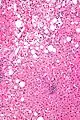

Micrograph showing a Mallory body. Original magnification 400X. H&E stain. Micrograph showing a Mallory body. Original magnification 200X. H&E stain.

Micrograph showing a Mallory body. Original magnification 200X. H&E stain. Liver micrograph showing abundant Mallory bodies, as seen in alcohol use disorder.